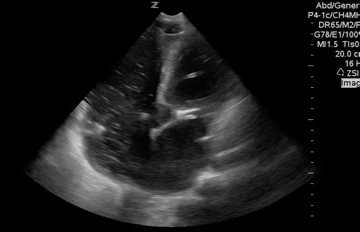

Here we have an apical 4 chamber view with right ventricle dilation, IV fluid and blood swirling in the right heart and basically no cardiac activity. It should only take three seconds to check the heart and minimize interruptions and CPR. It is far superior than palpating for a pulse and it can be prognostic as well as identify underlying arrhythmias.

The #POCUS pulse check. Better than palpation. Takes <3 sec, identifies arrhythmias and underlying etiologies #foamed #foamus